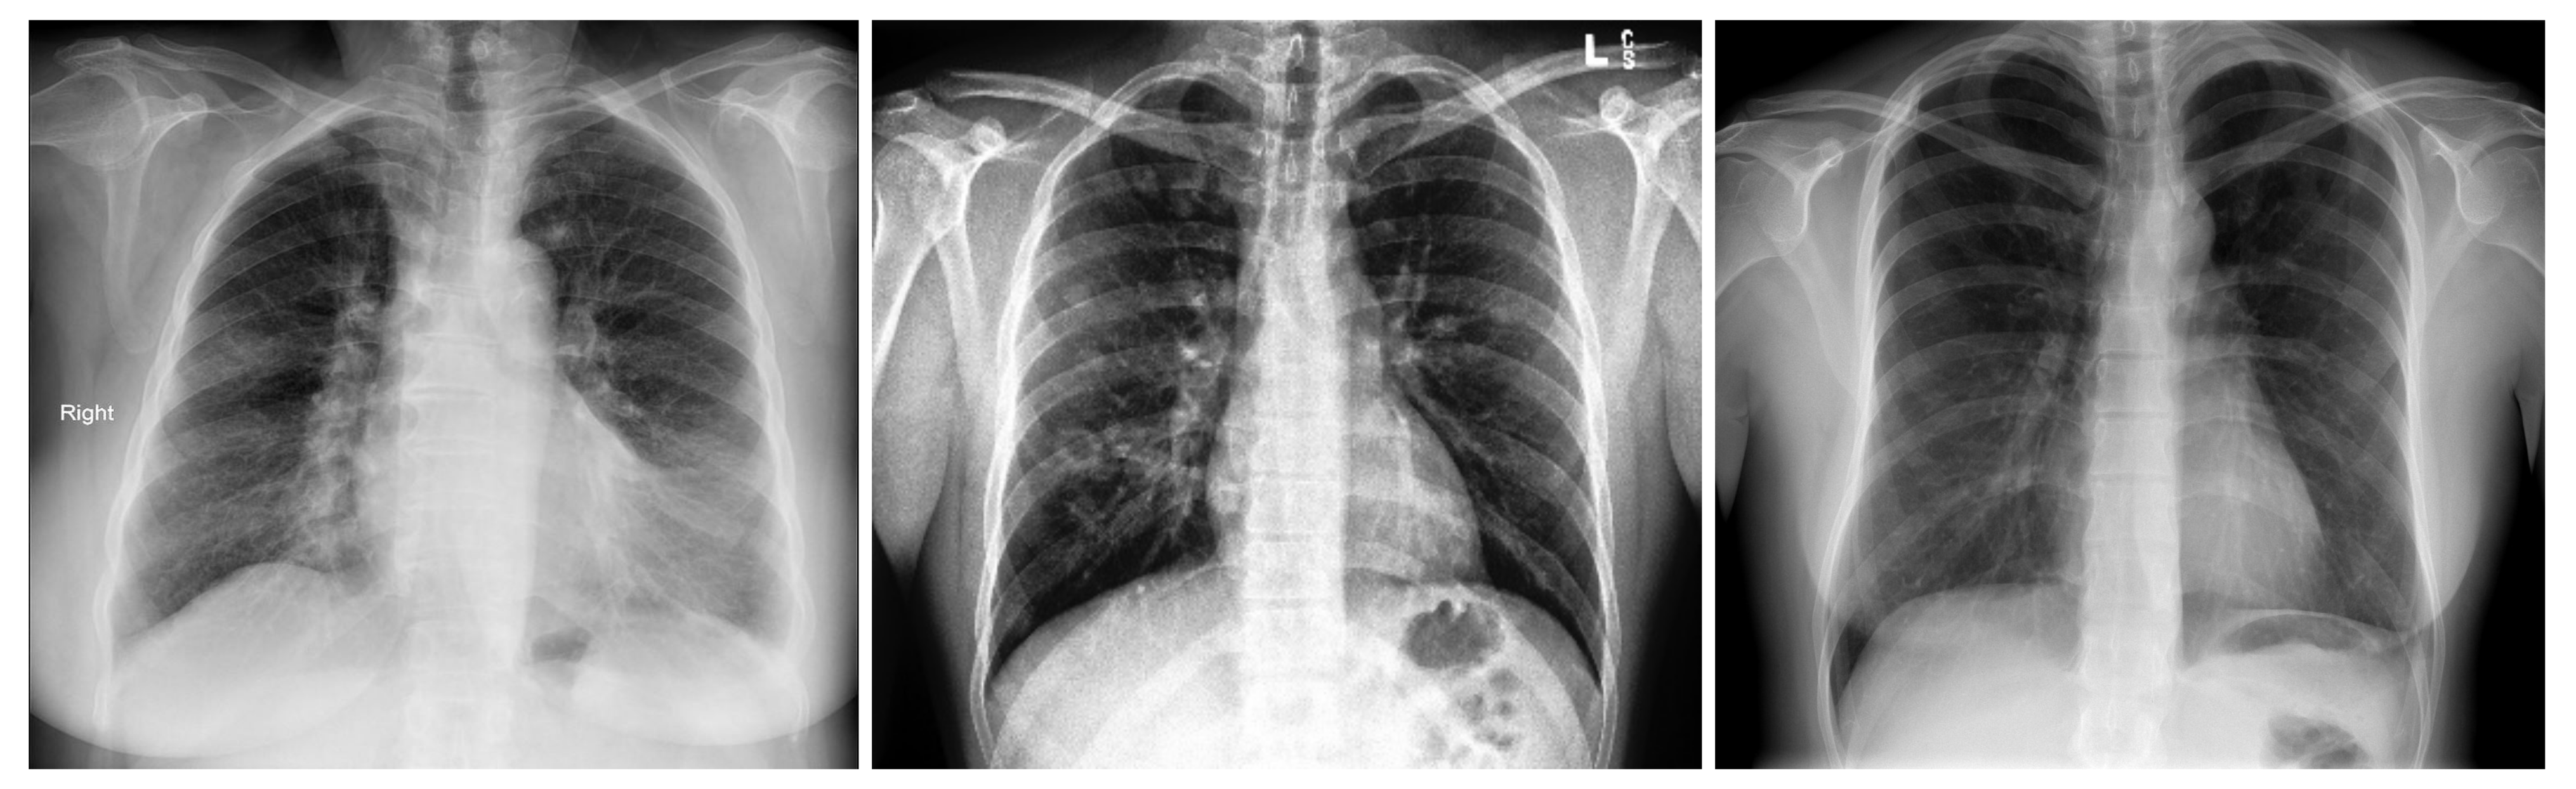

In order to distinguish between COVID-19 and the other lung diseases and healthy cases, we created a five-class COVID-19 database. In fact, COVID-19 is a viral pneumonia, so we aim to distinguish between Bacterial, Viral Pneumonia, COVID-19, and Healthy cases. In addition, we considered Lung Opacity Not Pneumonia diseases as the fifth class. Similar to the three-class COVID-19 database, we used data augmentation techniques to obtain augmented data to train our models. The same data augmentation techniques were applied for the training split to obtain 12 augmented images for each image. Table 3 summarizes the five-class COVID-19 database number of images by split and their resources. Figure 2 shows an X-ray example for each class of the five-class COVID-19 database.

Figure 2. In order: COVID-19, Viral Pneumonia, Bacterial Pneumonia, Lung Opacity, Normal.